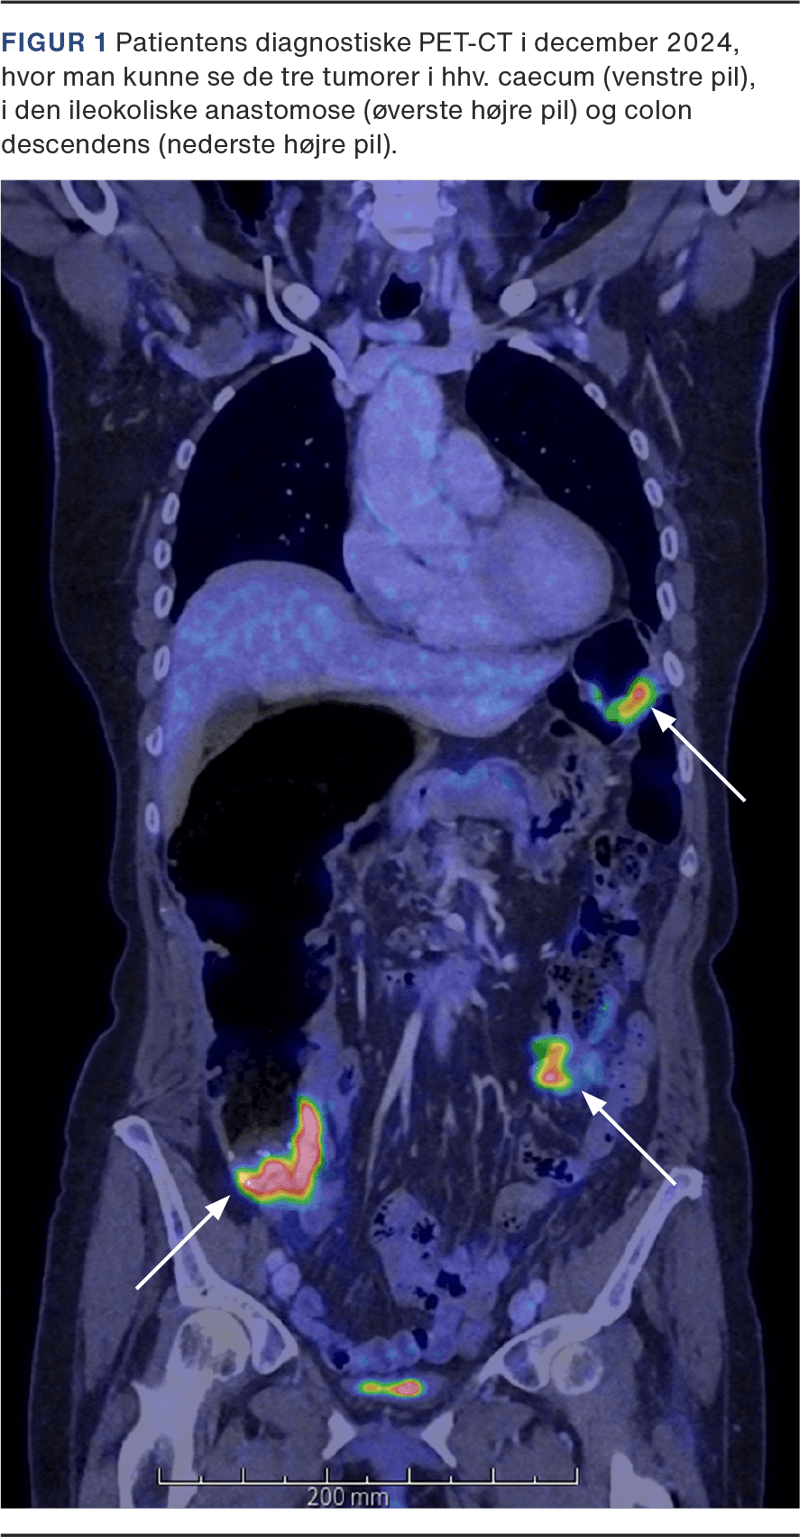

I marts 2019 blev en 67-årig kvinde diagnosticeret med mKRC med primær tumor lokaliseret i højre fleksur og metastaser i lymfeknuder (både over og under diafragma), lever, pancreas og peritoneum. Biopsier viste adenokarcinom med dMMR (immunhistokemisk manglende ekspression af pMLH1 og pPMS2, normal ekspression af pMSH2 og pMSH6) og BRAF-varianten, BRAF c.1799T>A (p.Val600Glu). Der blev påbegyndt pallierende behandling for patienten, hvor der på førstelinjebehandling med kemoterapi var progression med nytilkomne levermetastaser efter kun tre måneder. Derfor skiftede patienten til dengang eksperimentel andenlinjebehandling med pembrolizumab. Behandlingen var veltålt og succesfuld med hurtig regression af primær tumor, og efter 1,5 års behandling var der komplet respons (CR) radiologisk. Patienten blev i december 2020 indlagt med ileus pga. stenose svarende til tumorens lokalisation i højre fleksur. Patienten blev opereret med ileotransversostomi som omkørsel, da man vurderede, at man ikke kunne fjerne tarmsegmentet. I juni 2021 afsluttede patienten behandlingen og overgik til videre kontrolforløb med CT hver tredje måned. Denne viste initialt dilatation af colon ascendens, hvilket blev tolket som følger efter operationen. Grundet tiltagende dilatation blev patienten henvist til PET-CT og koloskopi i december 2024, hvor hun blev diagnosticeret med tre nye tumorer lokaliseret i hhv. caecum, den ileokoliske anastomose og colon descendens (Figur 1). Alle med dMMR i form af manglende ekspression af pMLH1 og pPMS2 og samme (hyppige) BRAF-variant som i den første tumor. Der var en del øvrige mutationer, som var forskellige – både imellem de enkelte tumorer og i forhold til den første tumor. Dette understøttede, at der var tale om tre nye primære karcinomer. PET/CT viste ingen metastatisk sygdom. Patienten fik foretaget radikal og ukompliceret subtotal kolektomi. Der blev for patienten planlagt tætte kontroller med CT og endoskopi. Patienten blev ydermere henvist til klinisk genetisk afdeling, hvor patienten på en blodprøve fik screenet flere gener relateret til KRC, men man fandt ingen genetiske disponerende faktorer for KRC.